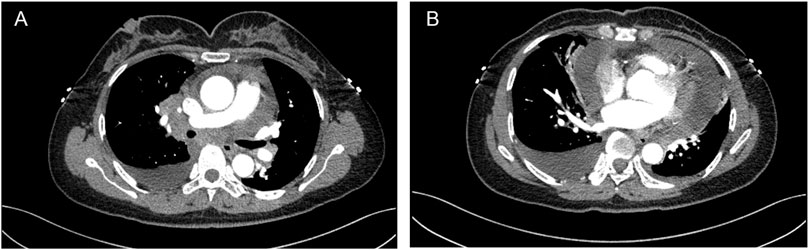

A 48-year-old female was admitted to a local hospital because of tussiculation and chest tightness on 23 March 2013. Chest computed tomography revealed a right hilar mass (Figure 1A), pleural effusion (Figure 1B), and pericardial effusion (Figure 1B). Right thoracic puncture and drainage were performed, and pleural effusion examination found adenocarcinoma cells. Needle aspiration cytology of the right supraclavicular lymph node indicated adenocarcinoma. The patient came to our center for further treatment on 31 March 2021. Cervical lymph node biopsy indicated metastatic adenocarcinoma which came from lung. Pericardiocentesis and drainage were performed, and pericardial effusion examination found adenocarcinoma cells. The patient was diagnosed with right lung adenocarcinoma with pleural and pericardial metastases (cT1N3M1a). Next-generation sequencing showed no driver gene mutations. On 1 April 2021, the patient received the first intrapericardial infusion of bevacizumab (300 mg). From April 8 to 17 August 2021, she completed six cycles of first-line therapy with pemetrexed and cisplatin combined with camrelizumab. This was followed by three cycles of camrelizumab maintenance therapy from September 9 to 22 October 2021. Due to disease progression, treatment was switched to sintilimab plus pemetrexed on 14 November 2021. Throughout this period, electrocardiograms and myocardial enzyme levels remained within normal limits, and the pericardial effusion was well-controlled, with only a minimal amount remaining. On 10 December 2021, the patients received the second intrapericardial infusion of 200 mg of bevacizumab due to worsening pericardial effusion. The following day (December 11), the patient developed acute chest pain. Myocardial enzymes (Figure 2) were significantly elevated and electrocardiography (Supplementary Data Sheet S1) showed ST-T changes and QTc prolongation. The N-terminal pro-brain natriuretic peptide level was 11,507 pg/mL and echocardiogram showed a normal ejection fraction. Bevacizumab-associated cardiotoxicity (myocardial ischemia) was initially suspected. Methylprednisolone, aspirin, and heparin were administered for treatment. The myocardial enzyme levels trended downward within 2 days, and the chest pain resolved after 10 days. Unfortunately, the patient died of central respiratory failure on 10 January 2022. Figure 3 presented the patient’s treatment timeline.

FIGURE 1

Chest computed tomography revealed a right hilar mass (A), pleural and pericardial effusion (B).